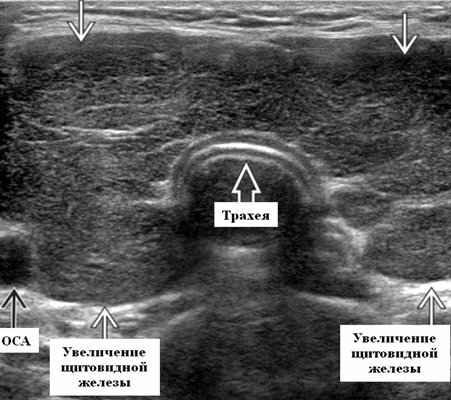

Начальное ультразвуковое сканирование (скаринование в B-режиме) должно быть осуществлено в поперечной плоскости, по сильным эхосигналам воздуха в трахее отмечая срединную линию, а крупные сосуды с обеих сторон используются как «ориентиры». После поперечного УЗИ шеи, дальнейшие исследования должны сопровождаться продольными сканированиями. Впоследствии, если имеется необходимость, может потребоваться исследование с цветным допплером всей щитовидной железы (болезнь Грейвса) или образований и увеличенных лимфатических узлов и опухолей, всегда после использования метода B-сканирования.

Щитовидная железа состоит из небольших долек, каждая из которых содержит около 25 фолликулов. Содержание фолликулов зависит от их функции. Это также определяет вид органа на УЗИ. По эхогенности вид щитовидной железы является однородным и эхогенным (нормофолликулярная стадия), что дает сильный контраст с более низким по эхогенности рисунком окружающих мышц, который может служить эталоном. Контур ровный и гладкий. Яркое эхо позади перешейка вызвано воздухом внутри трахеи. Сечение долей круглое или треугольное в поперечном сканировании и овальное в продольном направлении.

- Легкое / умеренное диффузное, симметричное увеличение щитовидной железы, включая перешеек на УЗИ

Серошкальное УЗИ при болезни Грейвса. Легкое или умеренное диффузное, симметричное увеличение щитовидной железы, включая перешеек. Увеличение в объеме щитовидной железы ≤ 90 мл. Нормальный объем: новорожденный 0,4-1,4 мл, увеличение на 1,0-1,3 мл на каждые 10 кг веса, до нормального объема 10-11 (± 3-4) мл у взрослых. Гипоэхогенный, гетерогенный, «пятнистый» паттерн паренхиматозной эхоструктуры. Гипоэхогенность паренхимы обусловлена снижением коллоидного содержимого и увеличением клеточного состава с уменьшением коллоидно-клеточной границы ± гиперваскулярность. Гипоэхогенность паренхимы связана с частотой позитивности антител к рецептору ТТГ (TRAb). Сохранение гипоэхогенности паренхимы при прекращении лечения, связанного с рецидивом гипертиреоза